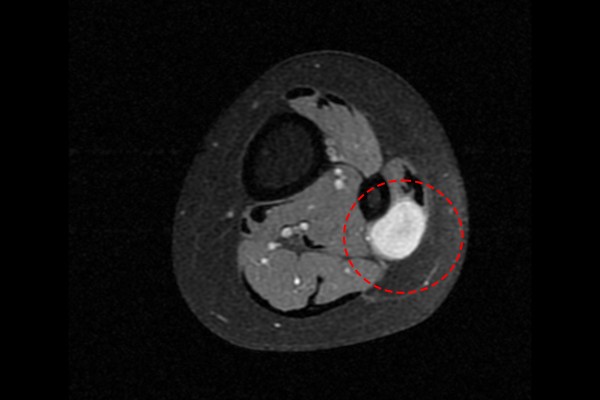

측면에서도 역시 종양이 확인되었고,

b1d6a7ed823268faf8290a31a2d8a8bb_1765960565_5408.jpg

단면에서도 신호변화를 확인하여, 좌측 발목 비골신경 신경초종[슈반종, 신경집종](Lt. ankle peroneal nerve Schwannoma[neurilemmoma])을 진단하였습니다.